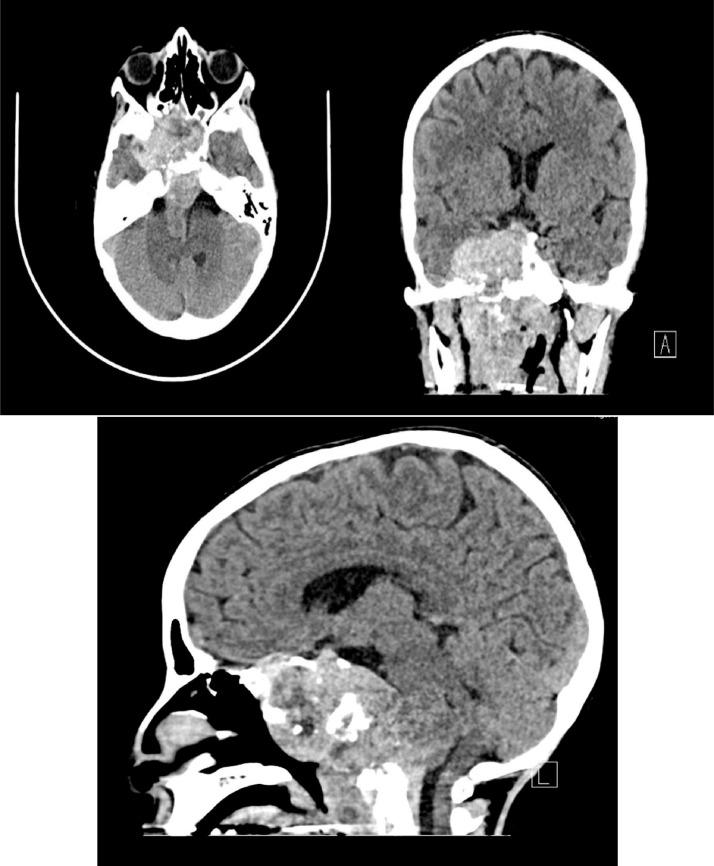

Chordoma is a rare and aggressive intracranial bone tumor that is difficult to diagnose and resect with a peak incident between the ages of 20-40 years old and high recurrence rate when not completely resected. We present the case of clival chordoma in an 11-year-old female patient, who reported with a chronic right-sided headache, progressive loss of vision, hoarseness of voice, and slurred speech. Fluid-fluid level on fluid-attenuated inversion recovery magnetic resonance imaging sequence can be an atypical radiological sign for clival chordoma. Thumbing of the pons as well as extension of the chordoma to the sinonasal, intracranial, vertebral, intraspinal, and orbital regions were observed. The patient underwent partial resection of the tumor and discharge home after by the end of the third week after the surgery. Histopathology report confirmed the diagnosis of chordoma.

脊索瘤是一种罕见且侵袭性的颅内骨肿瘤,难以诊断和切除,发病高峰在20至40岁之间,若未完全切除则复发率高。我们报告一例11岁女性斜坡脊索瘤患者,其症状为慢性右侧头痛、视力进行性丧失、声音嘶哑和言语不清。液体衰减反转恢复磁共振成像序列上的液-液平面可能是斜坡脊索瘤的一种非典型影像学表现。观察到脑桥拇指征以及脊索瘤延伸至鼻窦、颅内、椎体、椎管内和眼眶区域。患者接受了肿瘤部分切除术,术后第三周结束时出院。组织病理学报告证实为脊索瘤。